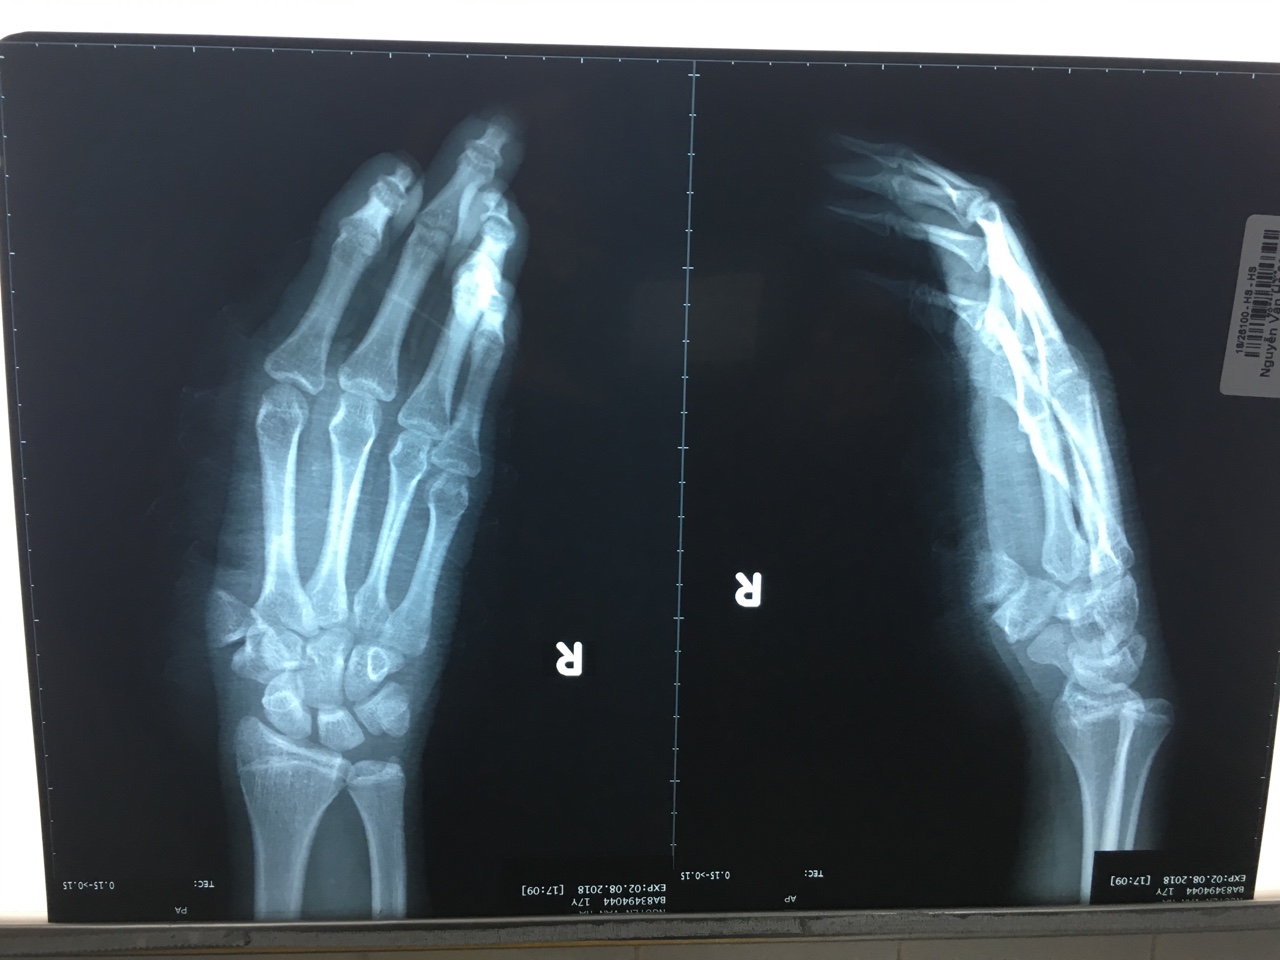

Khâu nối chi đứt lìa